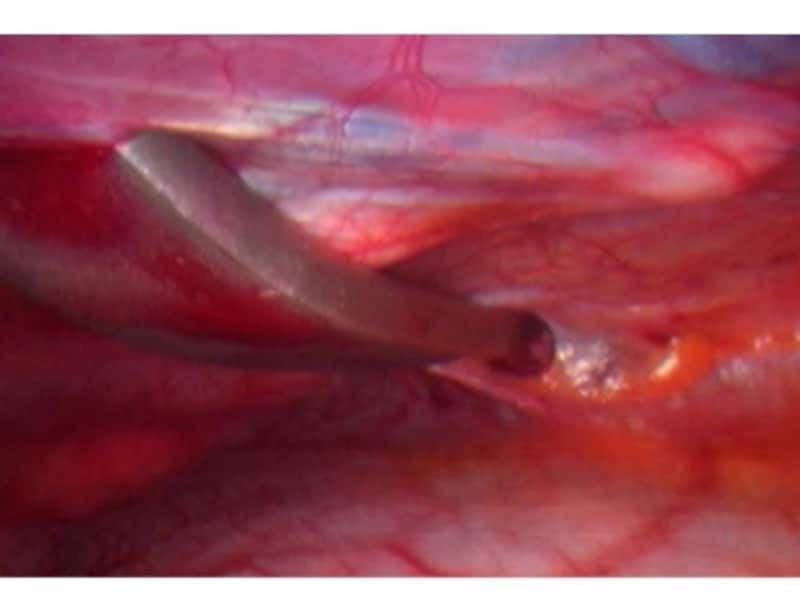

まず、細い金属の鉗子と呼ばれる道具を片側の胸腔内に挿入します。

胸の小さな傷から鉗子と呼ばれる細い道具を胸腔内に挿入します。

次にこの鉗子を反対側の反対側の胸腔内に誘導します。

鉗子の先端を反対側の胸腔内に誘導します。